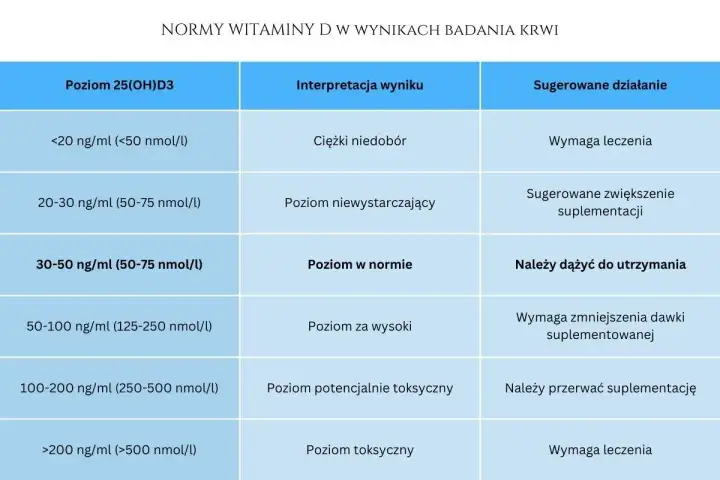

Dawka uderzeniowa witaminy D3 - kiedy i jak bezpiecznie?

Dawka uderzeniowa witaminy D3 – czy jest bezpieczna? Poznaj polskie wytyczne, ryzyka i zalecane dawki. Dowiedz się, kiedy potrzebna jest konsultacja z lekarzem.